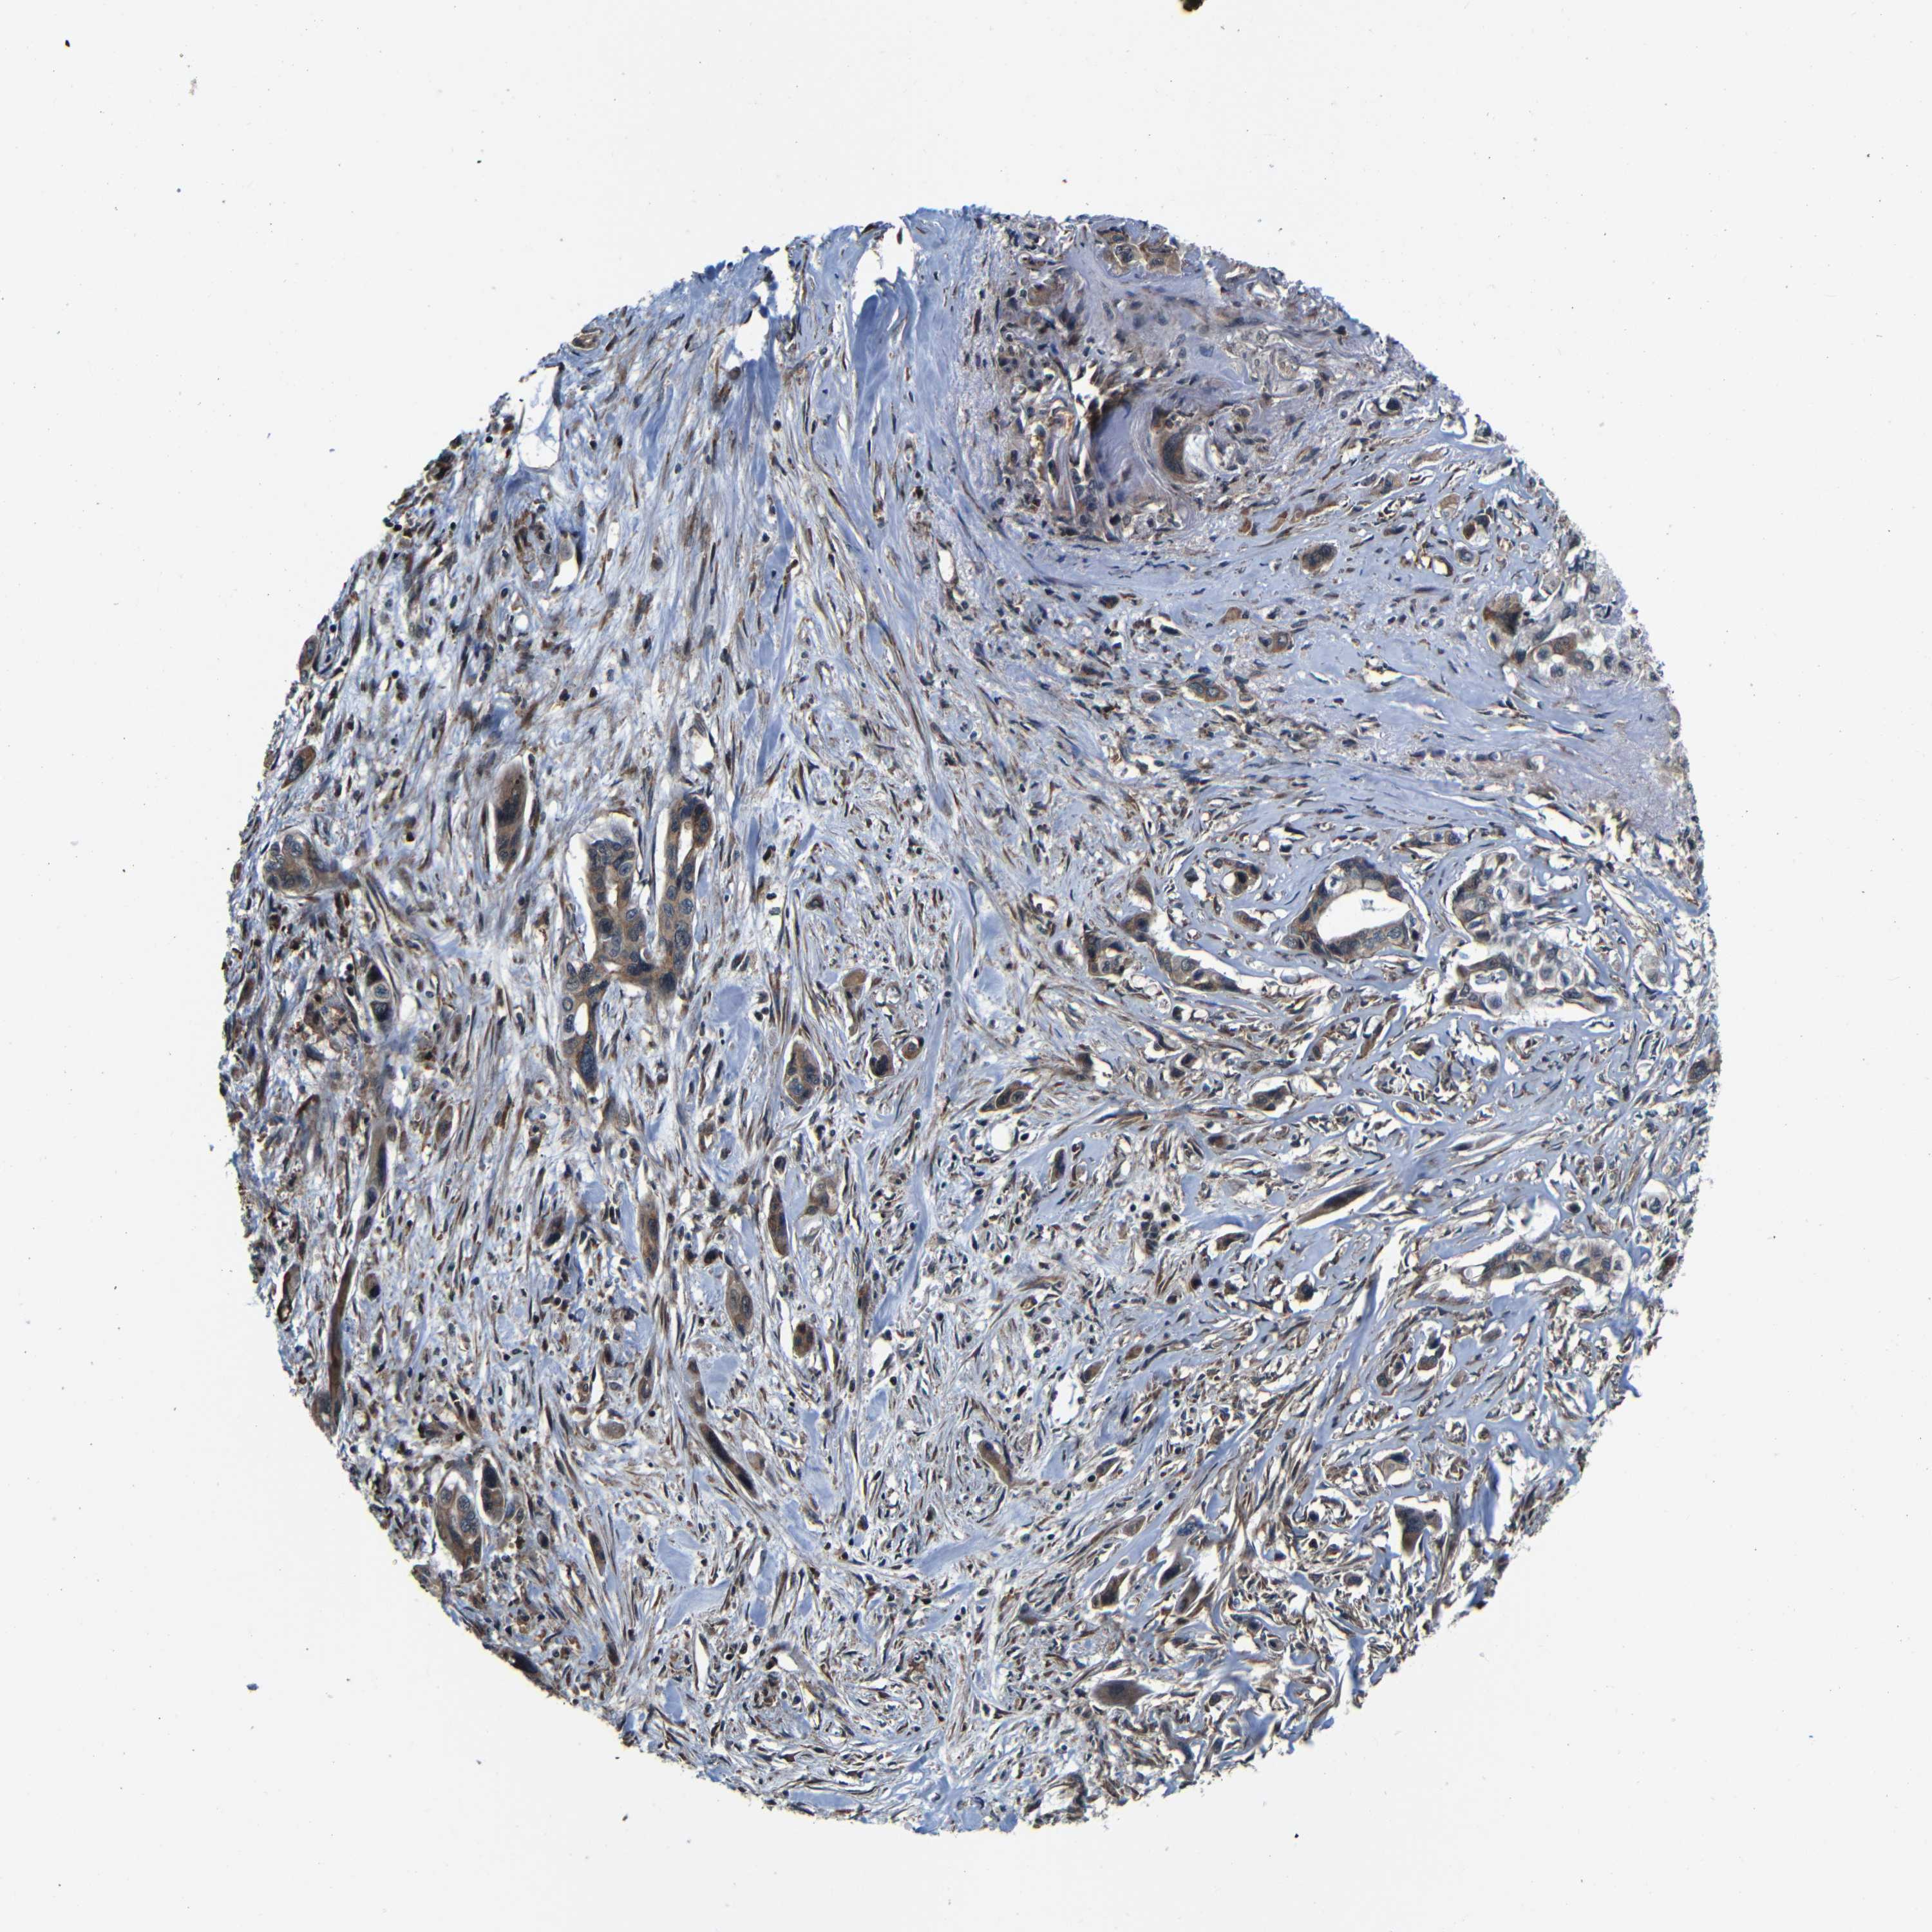

PANCREATIC CANCER - Protein expressioni

A mouse-over function shows sample information and annotation data. Click on an image to view it in a full screen mode. Samples can be filtered based on level of antibody staining by selecting one or several of the following categories: high, medium, low and not detected. The assay and annotation is described here.

Note that samples used for immunohistochemistry by the Human Protein Atlas do not correspond to samples in the TCGA dataset.

Antibody stainingi

Antibody staining in the annotated cell types in the current human tissue is reported as not detected, low, medium, or high, based on conventional immunohistochemistry profiling in selected tissues. This score is based on the combination of the staining intensity and fraction of stained cells.

Each image is clickable and will lead to virtual microscopy that enables deeper exploration of all samples and also displays staining intensity scores, fraction scores and subcellular localization as well as patient and tissue information for each sample.

Antibody HPA008959

Antibody HPA013195

Staining

High

Medium

Low

Not detected

Intensity

Strong

Moderate

Weak

Negative

Quantity

>75%

75%-25%

<25%

None

Location

Nuclear

Cytoplasmic/membranous

Cytoplasmic/membranous,nuclear

Adenocarcinoma, NOS